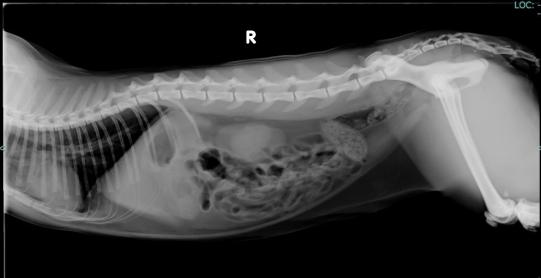

In der Klinik wird Blut untersucht und ein Röntgen angefertigt - hier ist ersichtlich, dass Leo Flüssigkeit im Brustkorb aufweist. Um das Atmen zu erleichtern wird die Flüssigkeit abpunktiert und zur Untersuchung eingeschickt. Im Blut finden sich Anzeichen einer Blutarmut sowie Verschiebungen in den Eiweissfraktionen (erhöhte Entzündungseiweisse und erniedrigte Albuminwerte). In der Brusthöhlenflüssigkeit finden sich mittels PCR-Untersuch Katzen-Coronaviren. Nun ist die Diagnose gestellt - Leo leidet an einer FIP (Feline Infektiöse Peritonitis).